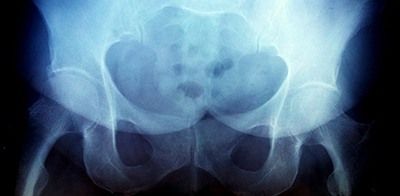

Рентгенография тазобедренного сустава

Тазобедренный сустав является сложным многоосным сочленением, которое выполняет сгибание/разгибание, отведение/приведение, пронацию и супинацию бёдер и принимает на себя серьёзную нагрузку. Любые нарушения в его функционировании не только приводят к серьёзному дискомфорту для человека, но и могут стать причиной развития серьёзных нарушений. Рентген тазобедренного сустава (ТБС) — это неинвазивный диагностический метод, ценность которого сложно переоценить.

Он нашёл широкое применение в разных областях медицины, включая травматологию, ревматологию, ортопедию, гнойную хирургию для диагностики заболеваний и последствий перенесённых травм, для определения объёма предстоящей операции или эффективности проведённого лечения. Процедура достаточно безопасна, высокоэффективна и проста, но при этом позволяет получить ценные данные о состоянии ТБС пациента.